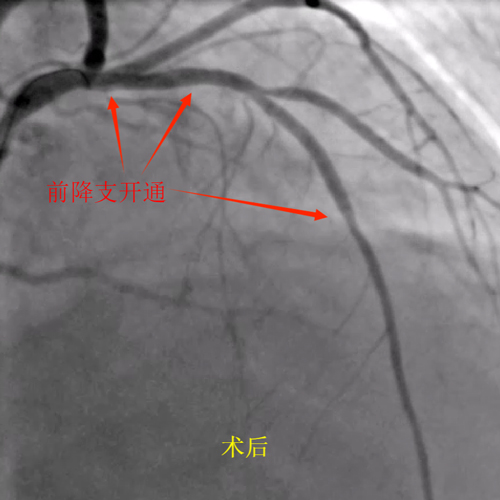

向某,71岁,1月4日因胸痛入院,诊断为急性非ST段抬高型心肌梗死。住院期间突发意识丧失,心血管内科团队立即识别,快速评估,确诊室颤,经有效心肺复苏及电除颤后抢救成功,病情稳定后获得家属同意完善冠状动脉造影,造影提示前降支闭塞。

随后,心血管内科介入团队成功为其植入支架,开通了闭塞的前降支。手术后,向某的症状明显缓解,并被安全送回心脏重症监护病房。